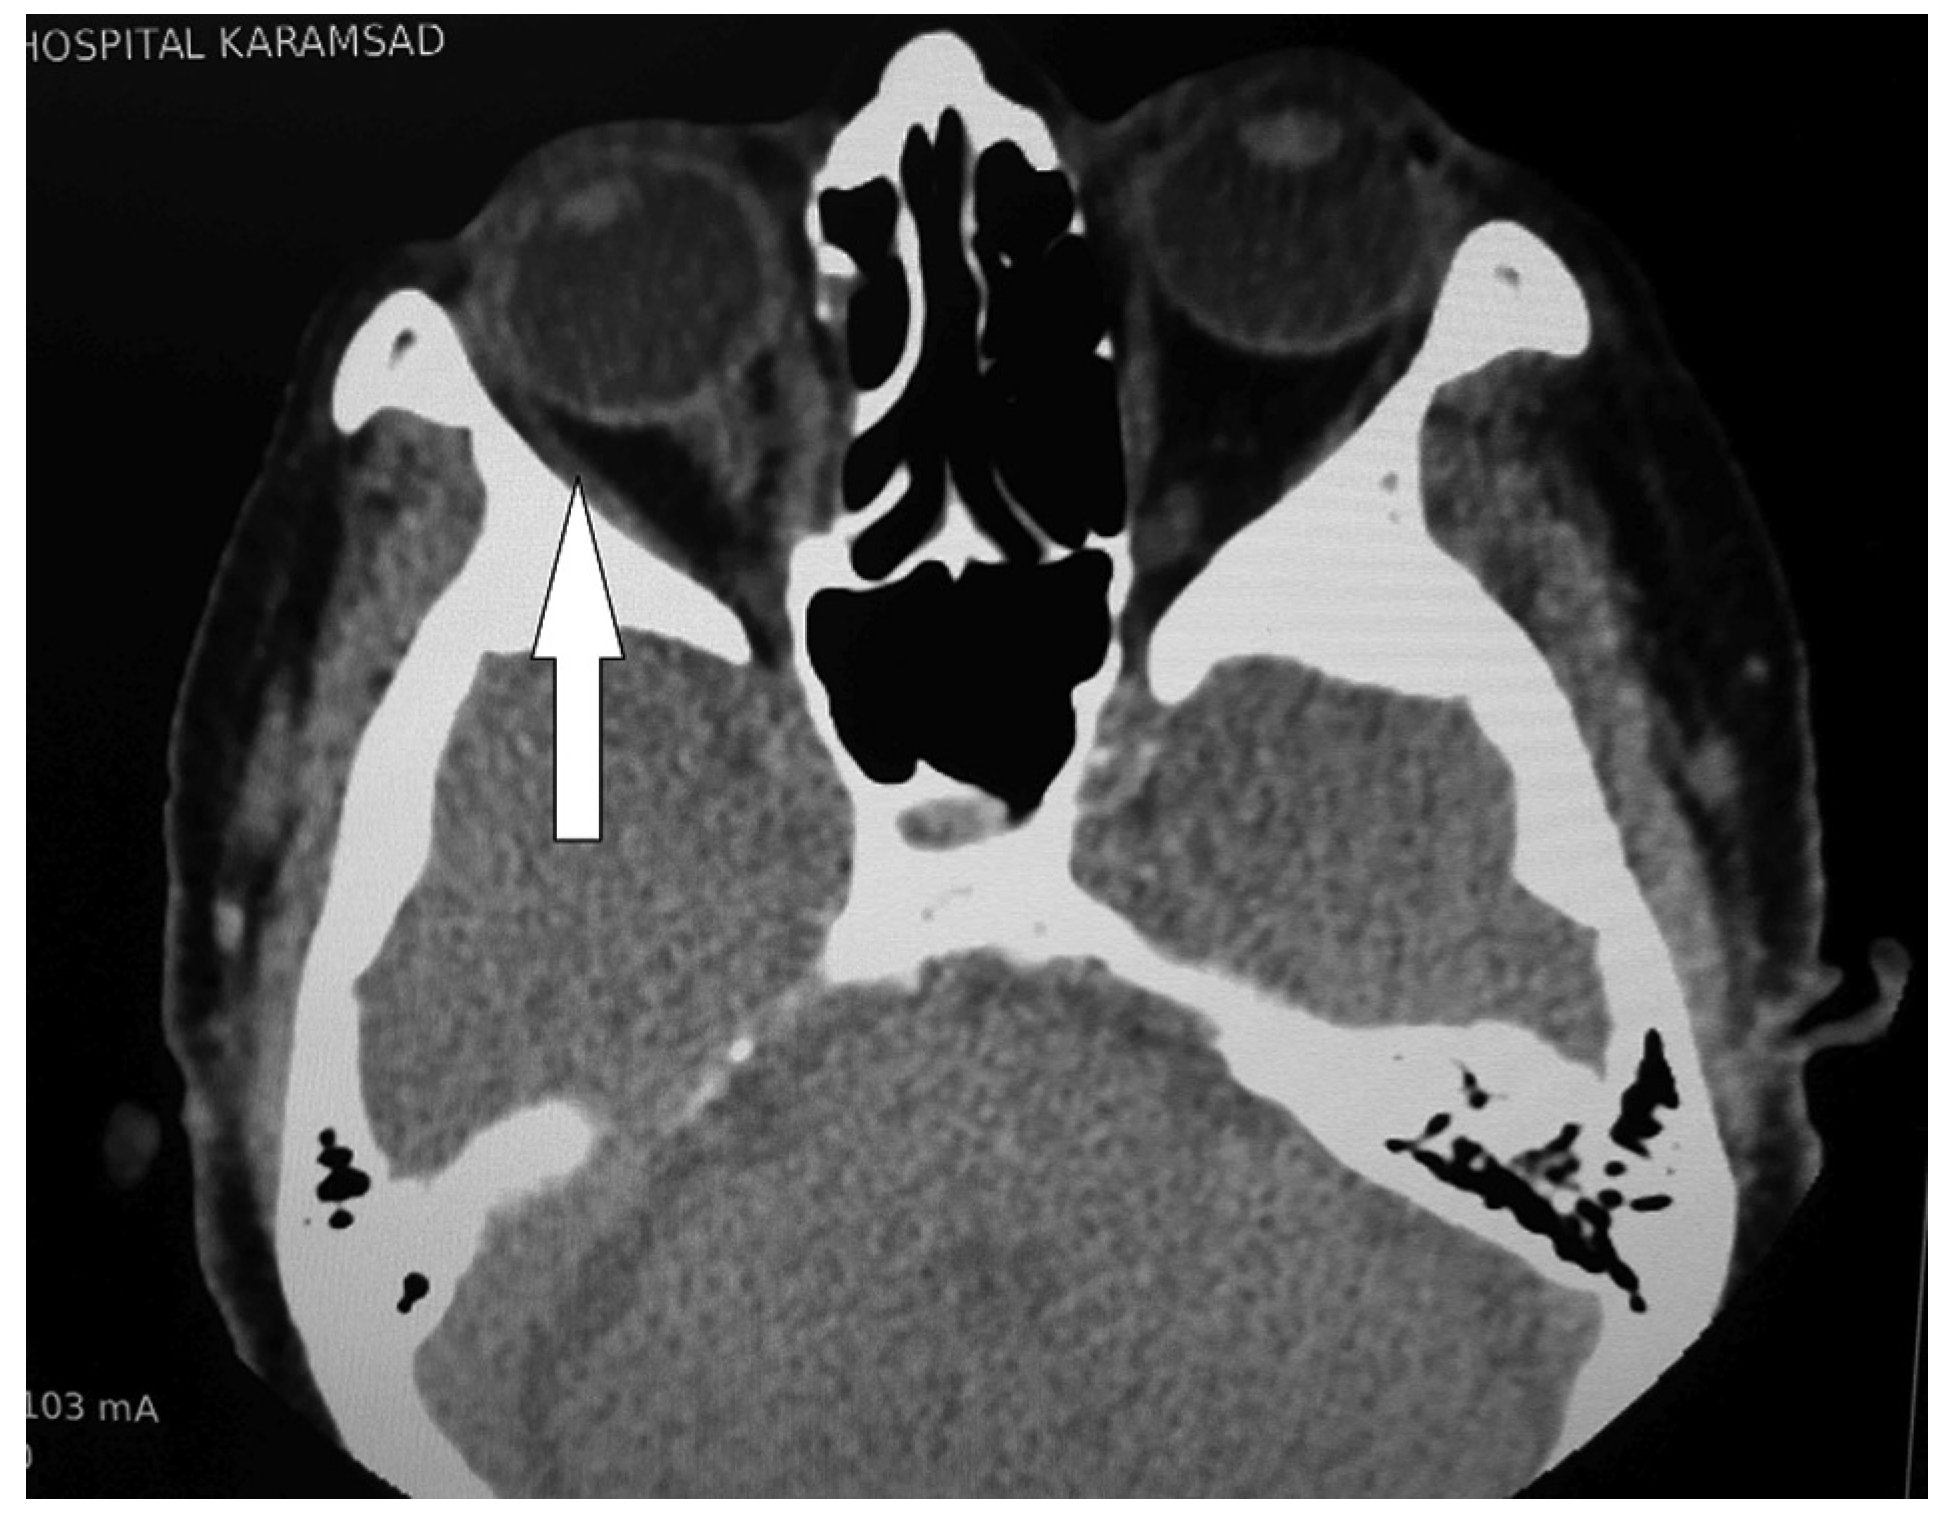

Diagnostic Assessment